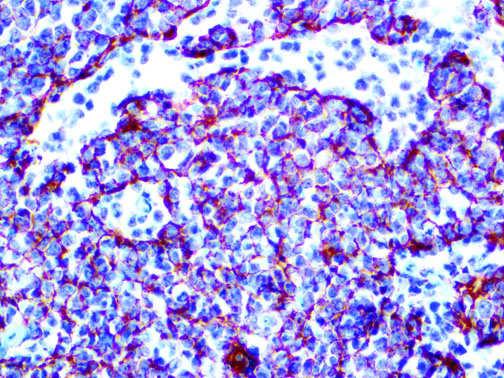

The first cytokines released are interleukin 1β (IL-1β) and tumor necrosis factor-α (TNF-α), which attract a variety of circulating white blood cells (WBCs) to the infection site, including neutrophils, monocytes, macrophages, and natural killer (NK) cells. This response, along with the antipathogenic chemicals released by these cells (i.e., complement), comprise the innate immune response. These cells directly attack the invading pathogen and also release additional cytokines, chief among them interleukin-1 and 6 (IL-6). IL-6 is essential for invoking the adaptive immune response, which calls T-cells, B-cells, and T helper (Th) cells to the infection site. IL-6 also stimulates further recruitment, proliferation and activation of macrophages.

It is the ICU physician who is most likely to witness one of the deadliest manifestations of the abnormal immunological response, the cytokine storm syndrome (CSS). This response is also referred to by some as the cytokine release syndrome (CRS). CSS is characterized by continuous activation and expansion of macrophage and lymphocyte populations, which secrete large amounts of cytokines, causing the cytokine storm. This massive cytokine release is akin to hemophagocytic lymphohistiocytosis (HLH) disease, a syndrome characterized by initial unchecked and persistent activation of cytotoxic T lymphocytes and NK cells.

This activation induces inflammatory monocytes to highly express IL-6, starting a localized and then systemic cascade effect that results in hyperproduction of IL-6, which accelerates the inflammatory process. Because IL-6 also increases vascular permeability, excessive levels cause blood vessels to become very leaky. This, along with clotting factors released from vascular endothelial cells, stimulates the coagulation cascade, resulting in microthrombosis (tiny clots), which leads to ischemia and tissue death of the kidney, intestines, heart, liver, brain and extremities.